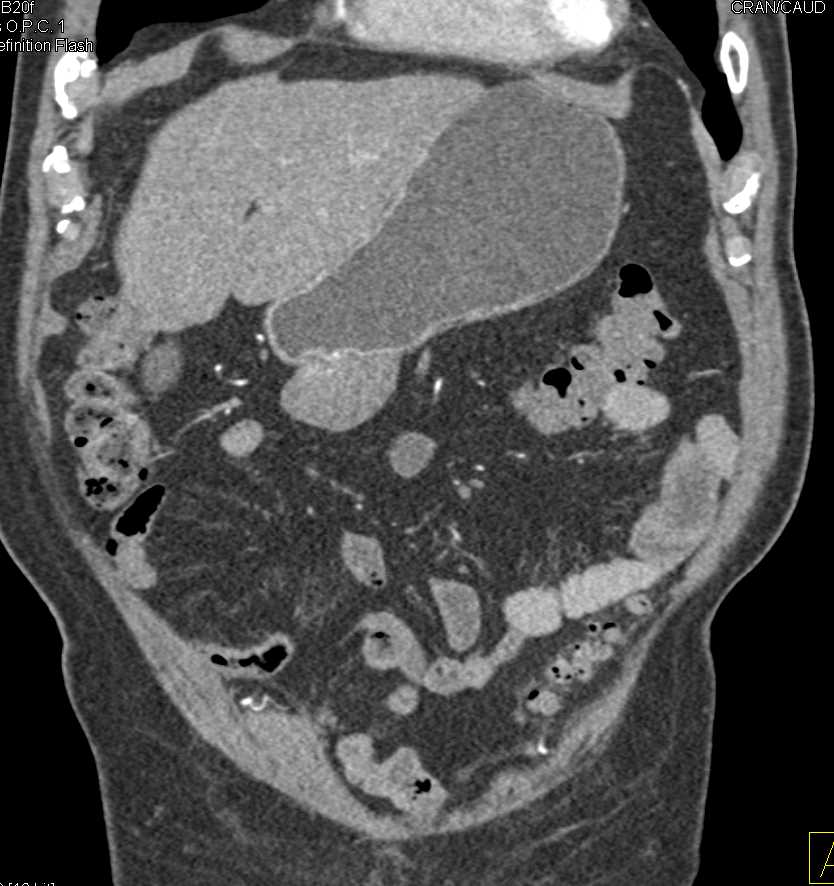

Exophytic Gastric GIST Tumor